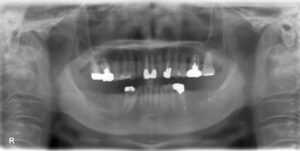

下顎前歯1本・臼歯3本欠損症例

BEFORE AFTER 54歳女性/下4本欠損/インプラント埋込手術 【治療内容】 右下中切歯の歯周病が重度まで進行し…